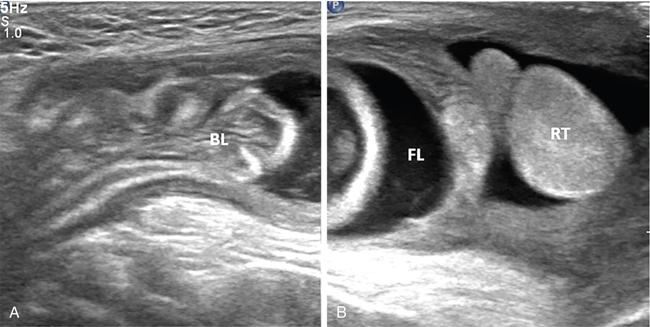

2. Imbalance of production and reabsorption of fluid within tunica vaginalis space in scrotal sac. This disturbance may be a result of infection, tumour, trauma, torsion, defective lymphatic drainage after surgery for varicoceles and inguinal hernias or idiopathic (Fig. 11.8.10).

Fig. 11.8.10Combined right inguinoscrotal US images of an infant showing a hernia sac extending up to supra testicular location containing fluid (FL) and herniated bowel loops (BL), consistent with inguinal hernia.